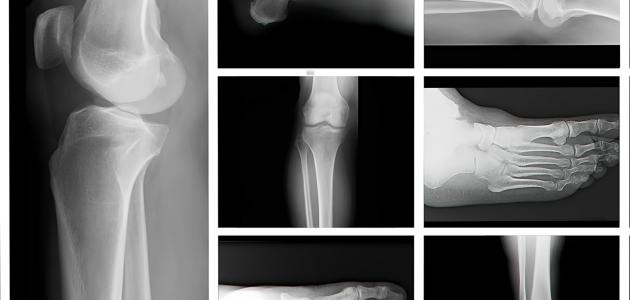

هشاشة العظام

توجد في العظام في الوضع الطبيعي مسافات صغيرة، وعند زيادة حجم هذه المسافات عن الحدّ الطبيعيّ تقل قوة العظام وكثافتها، ويصبح الجزء الخارجي من العظام أضعف وأقل سمكاً، وهذا ما يُعرف ببساطة بمرض هشاشة العظام (بالإنجليزية: Osteoporosis)، ويُعدّ هذا المرض الذي يُصيب العظام من الأمراض الشائعة، إذ قُدّر عدد المصابين به في الولايت المتحدة الأمريكية والذين ترتفع احتمالية إصابتهم به بما يُقارب 53 مليوناً، وعلى الرغم من أنّ مرض هشاشة العظام قد يُصيب الأفراد بغض النظر عن أعمارهم، إلا أنّه غالباً ما يؤثر في الأسخاص الكبار في السنّ وخاصة النساء، ومن الجدير بالذكر أنّ مرض هشاشة العظام يتسبّب بمعاناة المصاب من كسور العظام، إذ تكون العظام أكثر عُرضة للكسور حتى خلال ممارسة الأنشطة اليومية مثل الوقوف والمشي، وتجدر الإشارة إلى أنّ عظام المعصم، والعمود الفقري، والورك، والقفص الصدريّ الأكثر شيوعاً للإصابة بالكسور في الأشخاص الذين يُعانون من هشاشة العظام.[١]